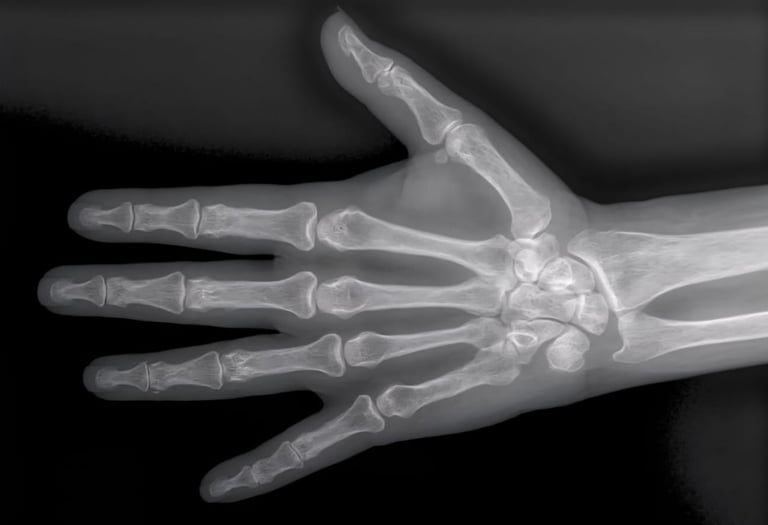

Hand X-rays

Detailed digital imaging for hand, wrist, and finger injuries or joint conditions. We provide high-resolution views for fracture diagnosis and orthopedic assessments with fast reporting.